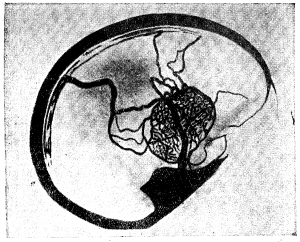

§ 7. Связь вен спинного мозга с общей венозной системой

Подобно тому как артериальную кровь спинной мозг получает не из одного какого-либо ствола, а из многих метамерных стволов, так и венозную кровь он отдаёт не в один какой-либо ствол, а во многие метамерные вены. Есть два направления, по которым венозная кровь может покидать спинной мозг: пути черепа и пути позвоночника. В череп венозная кровь из позвоночника может попасть через описанные выше анастомозы венозных трактов с венами продолговатого мозга и черепно-мозговых нервов, а также через позвоночные вены, связанные с затылочно-позвоночным сплетением. Принимая во внимание, что в спинно-мозговых венах нет заслонок, нужно думать, что венозная кровь попадает в череп только из верхнего отдела спинного мозга, а основная масса крови выходит иными путями: вены спинно-мозговых нервов выносят кровь во внешнее венозное сплетение позвоночника и отчасти во внутреннее, с которым эти вены анастомозируют. Отсюда кровь через межреберные, поясничные и крестцовые вены попадает в систему нижней и верхней полой вены.

Внепозвонковые вены образуют по задней поверхности позвоночника очень сложное сплетение, в которое, помимо вен спинного мозга, вливается ещё множество вен из спинной мускулатуры. От этого сплетения, покрывающего широкими, неправильными петлями дуги позвоночника, отходят анастомозы к заднему внутреннему сплетению, проникая в полость позвоночника через жёлтую связку. Большая часть оттоков заднего внепозвоночного сплетения направляется вдоль поперечных отростков позвонков, проходит между отростками и впадает в межреберные вены или же (в Шейной области), сливаясь в один ствол, образует позвоночную вену, во всех отношениях аналогичную одноимённой артерии. На передней поверхности позвоночника описывается несколько внепозвоночных вен, исходящих из позвонков и связок позвоночника; эти слаборазвитые стволики впадают в соседние стволы, главным образом, в непарную вену (рис. 4, 5).

Исключительно интересны исследования Долго-Сабурова о значении венозной системы позвоночника как окольного пути, соединяющего верхнюю и нижнюю полую вену. Благодаря этому пути, может осуществляться ток венозной крови при наличии препятствий в системе одной из полых вен: через окольные пути кровь попадает в оставшуюся проходимой полую вену и таким образом — в сердце. При нарушении кровотока во внутренних яремных венах кровь из синусов твёрдой мозговой оболочки может попасть через анастомозы в оба позвоночных сплетения и таким окольным путём доходить до сердца. Спинальные вены являются частью вертебрального окольного пути.